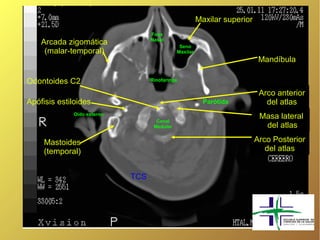

Maxilar superior Fosa Nasal Arcada zigomática Seno (malar-temporal) Maxilar Mandíbula Odontoides C2 Rinofaringe Arco anterior Apófisis estiloides Parótida del atlas Oído externo Masa lateral Canal Medular del atlas Mastoides Arco Posterior (temporal) del atlas TCS